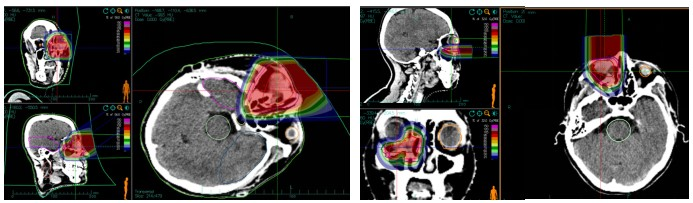

Treatment Plan Implementation:The carbon ion radiotherapy plan involved the patient lying in a supine position, fixed with a vacuum bag and thermoplastic film. CT and MRI images were fused to delineate the target volume. The gross tumor volume (GTV) included the visible right lacrimal sac lesion on enhanced T1-weighted images. The clinical target volume (CTV) encompassed the GTV, right medial rectus muscle, right ethmoid sinus, and right maxillary sinus. Planning target volume 1 (PTV1) was the GTV + 0.3 cm, and PTV2 was the CTV + 0.3 cm. The prescribed dose was 64 Gy (RBE) in 16 fractions for PTV1 and 56 Gy (RBE) in 14 fractions for PTV2. Organs at risk (OAR) dose constraints were as follows: right eye: mean dose ≤ 30 Gy (RBE), right lens: left eye: maximum dose ≤ 9 Gy (RBE), brainstem: maximum dose ≤ 54 Gy (RBE), right optic nerve: 50% isodose line ≤ 56 Gy (RBE), right temporomandibular joint: mean dose ≤ 35 Gy (RBE), optic chiasm: maximum dose ≤ 54 Gy (RBE), left eye: mean dose ≤ 35 Gy (RBE), left lens: maximum dose ≤ 0 Gy (RBE).

Figure 3: First course horizontal field: Prescription dose PTV 56 Gy (RBE)/14 fx; Second course vertical field: Prescription dose PTV = 8 Gy (RBE)/2 f.